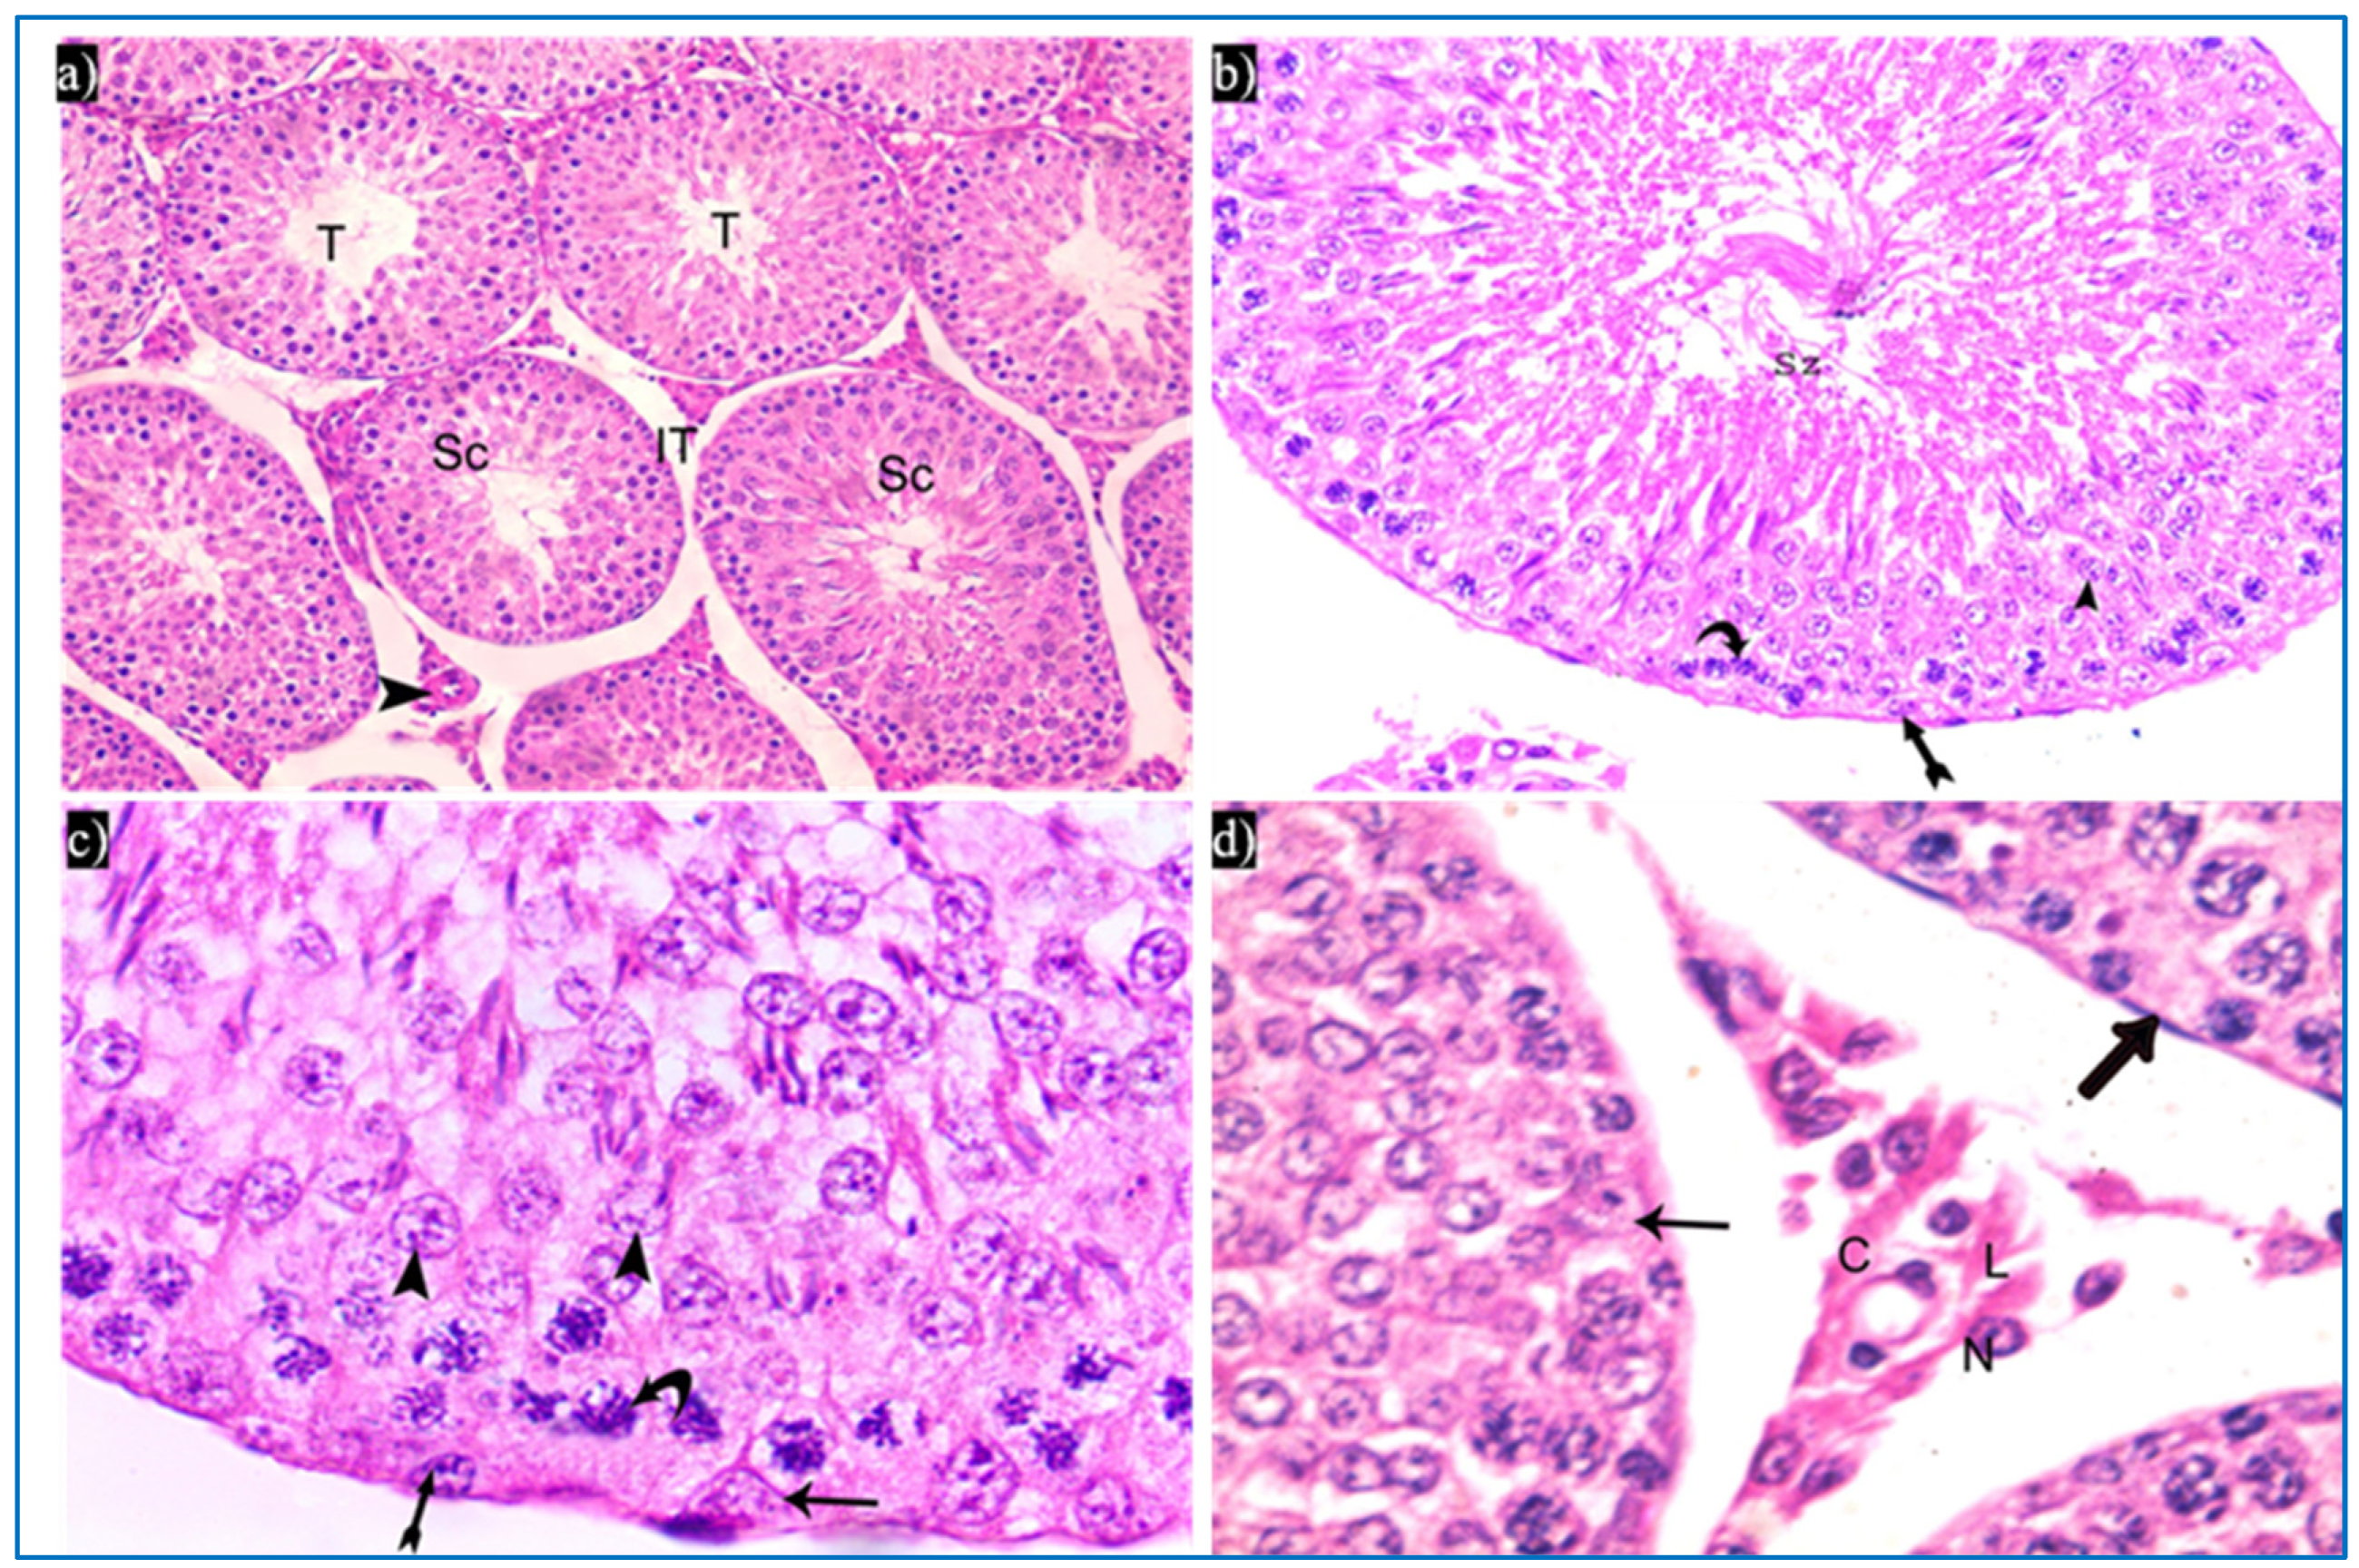

3.1.1. Hematoxylin and Eosin

3.1.2. Periodic Acid-Schiff’s Reaction (PAS)